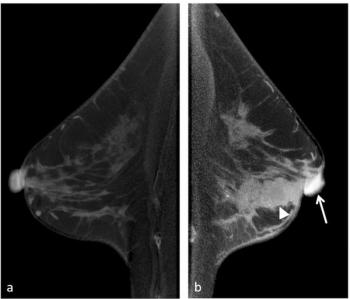

Preoperative use of contrast-enhanced cone-beam breast CT has over a 96 percent sensitivity for predicting nipple-areolar complex involvement in cases involving early-stage breast cancer, according to a new study.